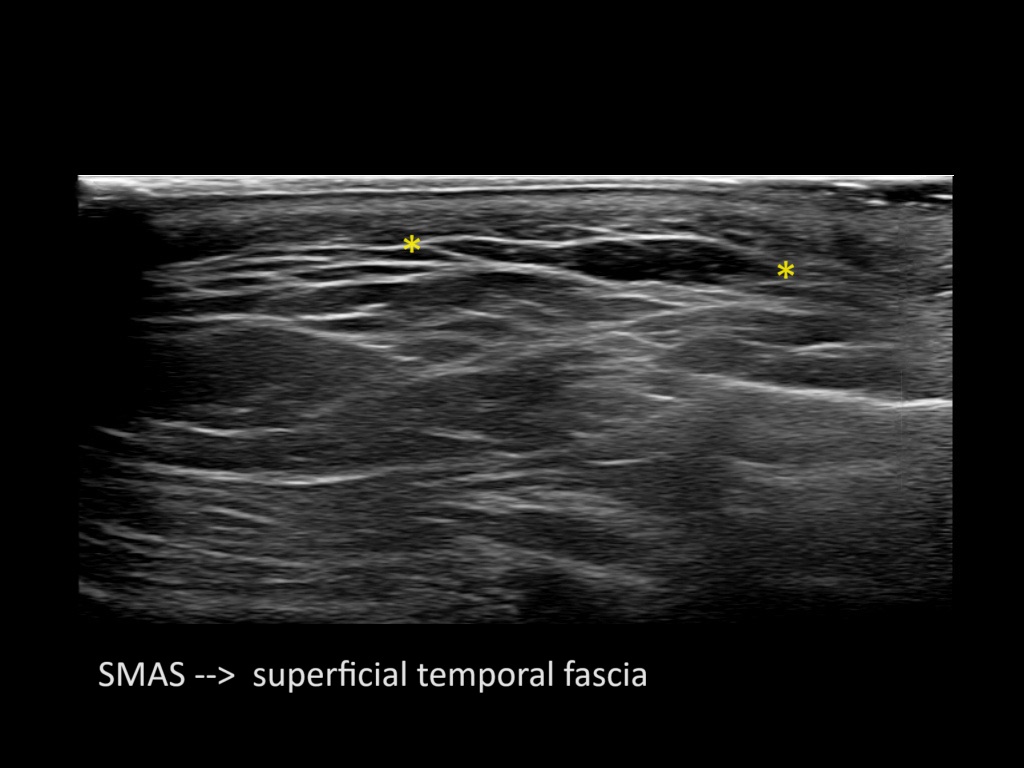

Filler behavior - Temple zygoma US

Study the first image to recognize the different layers. If you are sure about the layers, swipe to the second image to view the answer (if applicable).

Hover over an image to view the secondary image or click on the image title for more information.